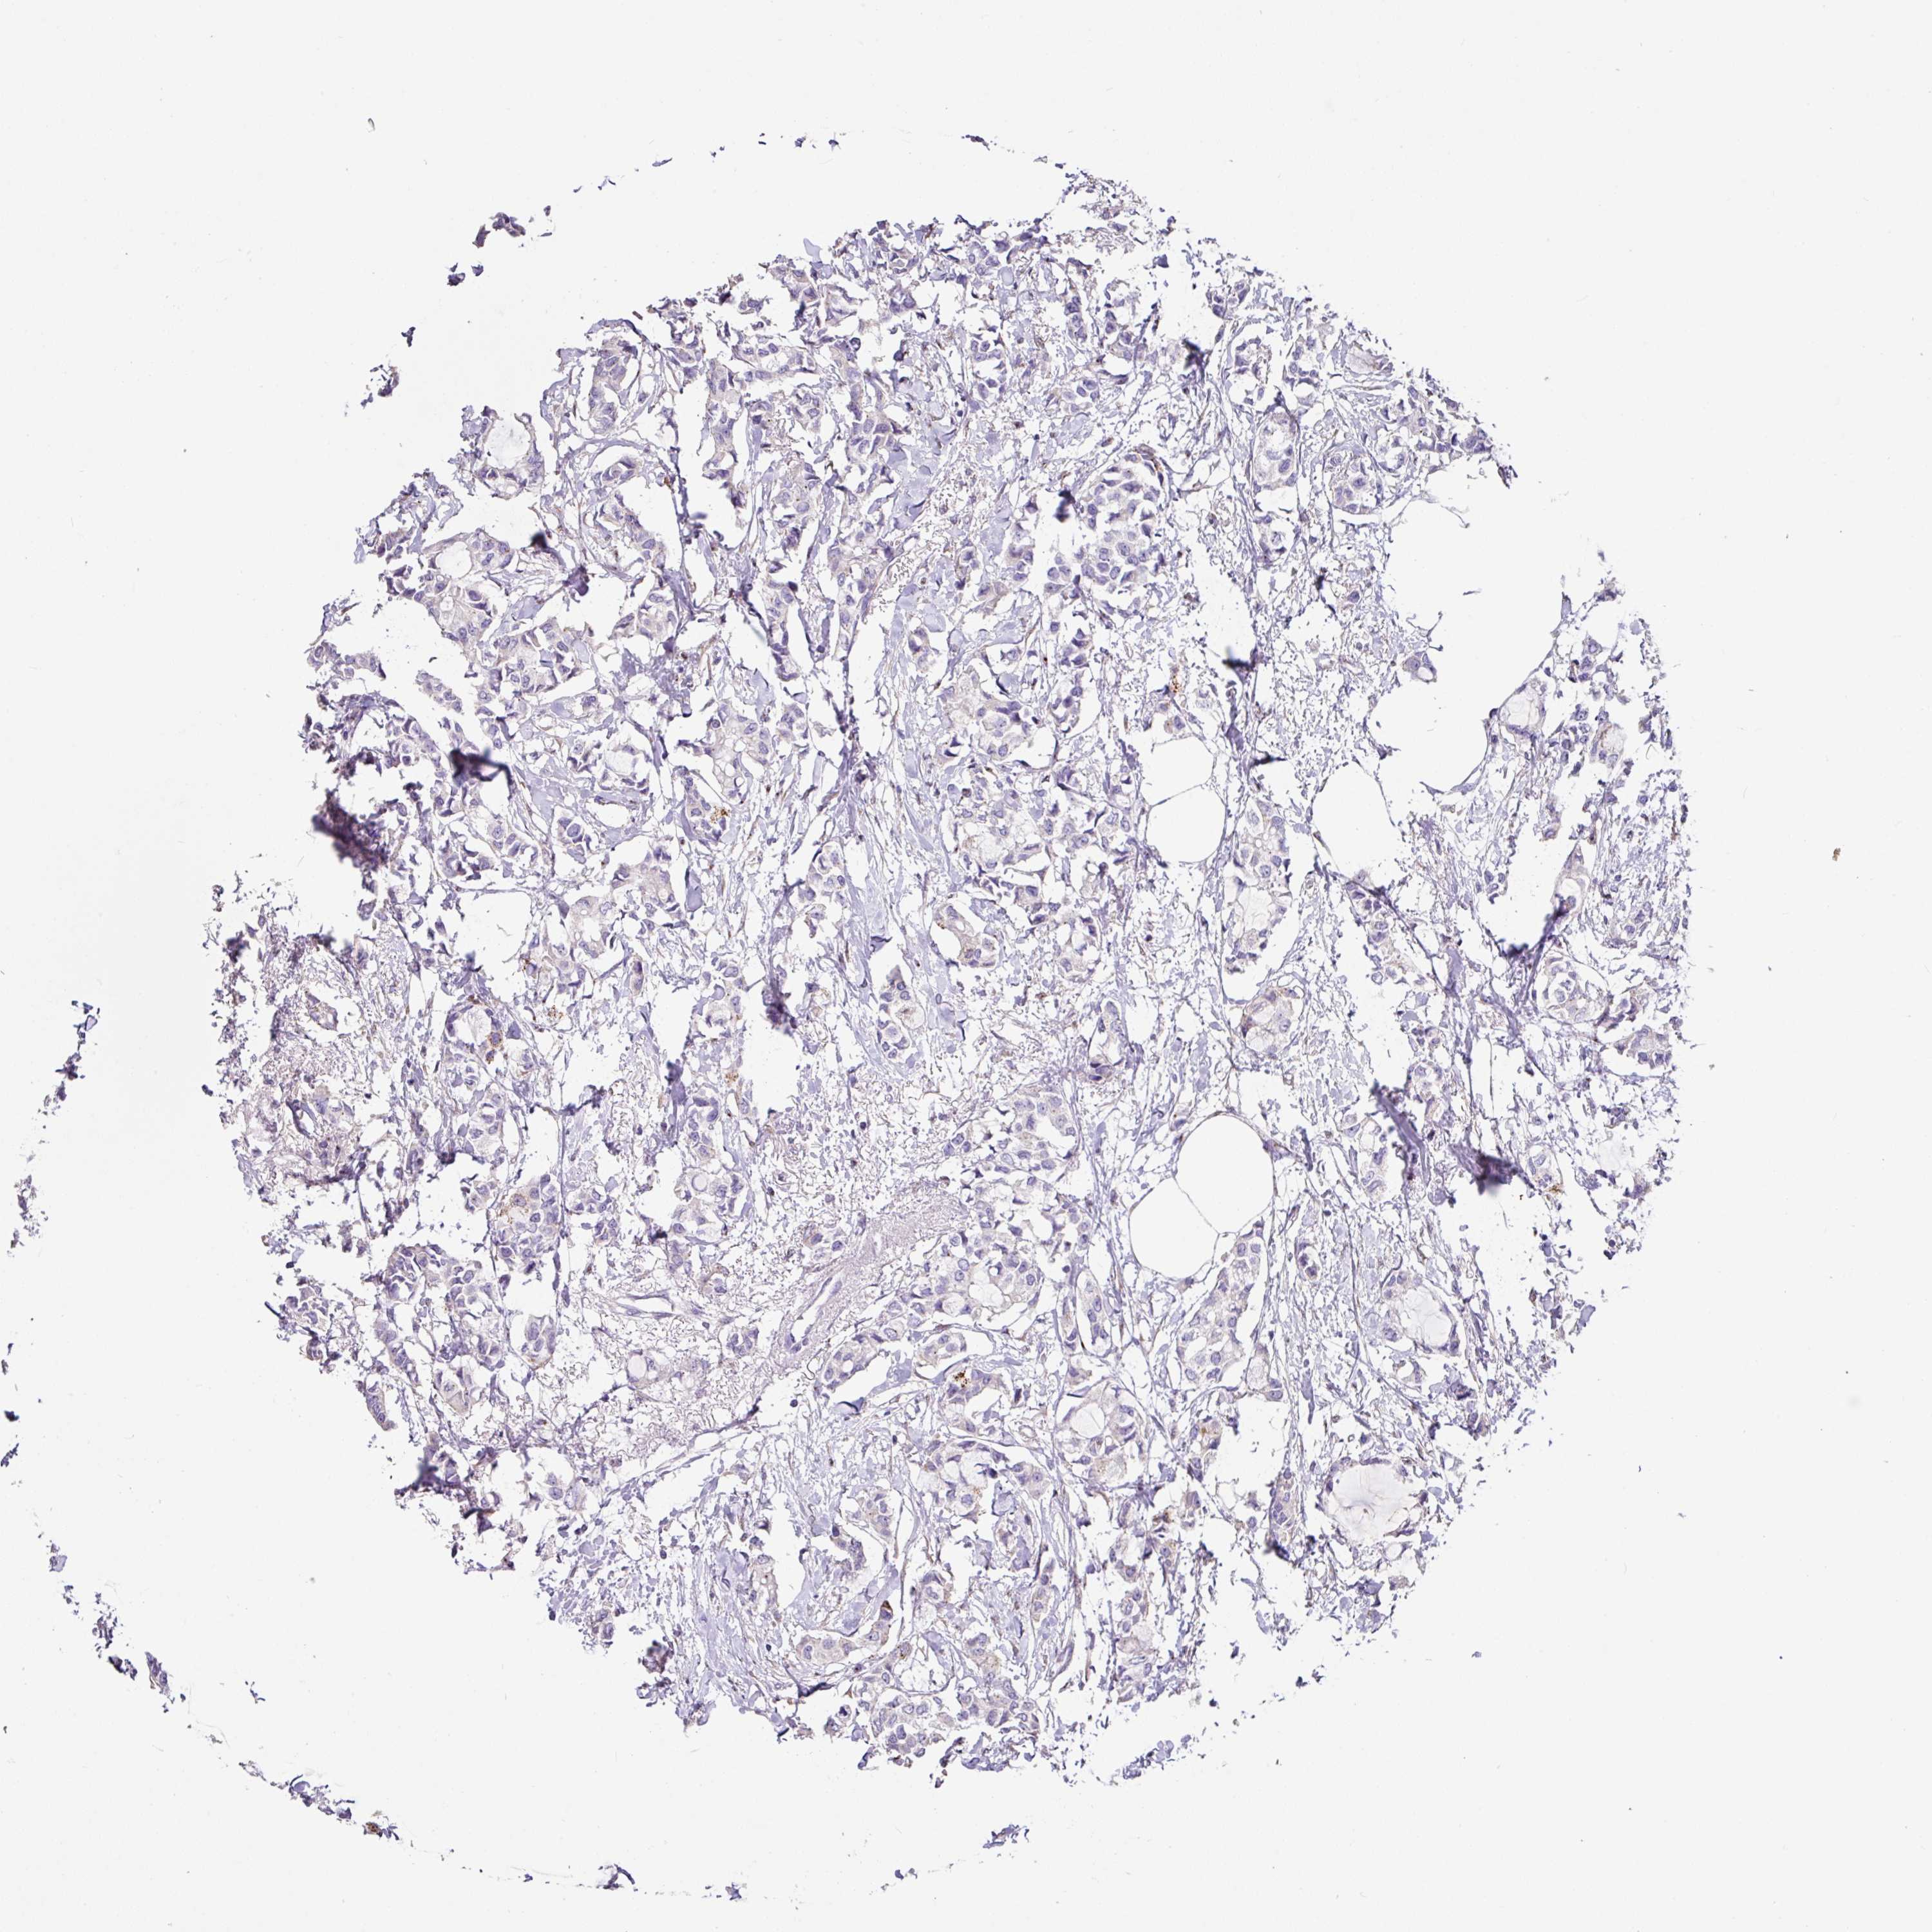

BRCA TCGA BRCA VALIDATION PROTEIN EXPRESSION